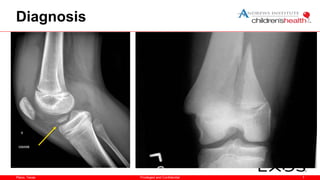

Diagnosis

• Always X-ray an athlete with a traumatic effusion

– Physeal (growth plate) fracture

– Patellar dislocation

– Osteochondral fracture

– Tibial spine avulsion